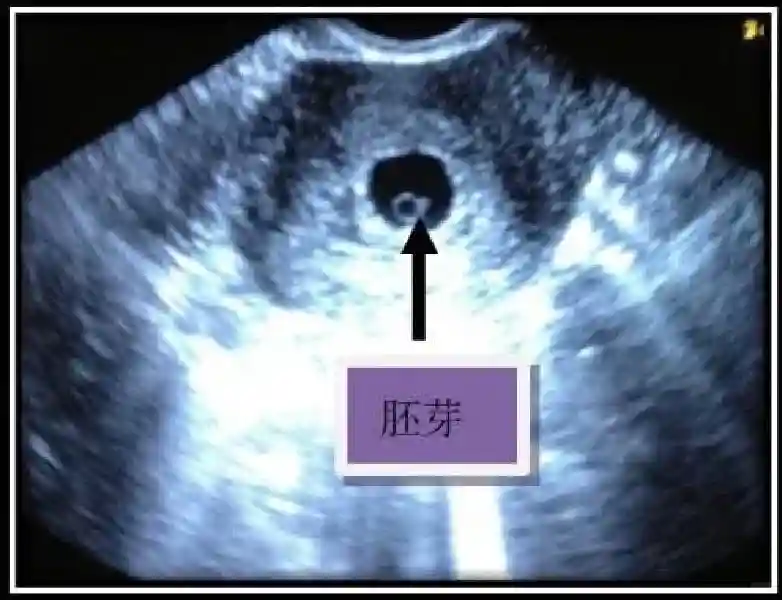

3??胚胎:胚胎通常在6-7周时可以为超声显示,起初为胎芽,表现为卵黄囊一侧局部组织增厚,达到1 -2 mm 时才有可能为超声测量出来。达4-5mm时可见胎心搏动,相应孕周为6-6.5周,妊娠囊大小为13-18mm。胚芽长度≥7㎜时仍未见心管搏动,提示胚胎停止发育。胚胎的出现和妊娠囊直径的关系:妊娠囊直径> 16 mm 时,经阴道超声应显示胚胎。妊娠囊直径> 25 mm 时,经腹超声均应显示胚胎。